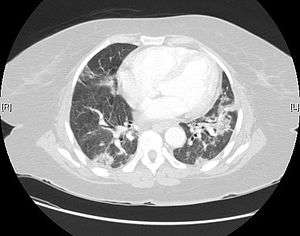

Usual interstitial pneumonia seen on CT scan. Honeycomb fibrosis is seen at the bases of both lungs.

UIP may be diagnosed by a radiologist using computed tomography (CT) scan of the chest, or by a pathologist using tissue obtained by a lung biopsy. Radiologically, the main feature required for a confident diagnosis of UIP is honeycomb change in the periphery and the lower portions (bases) of the lungs.[2] The histologic hallmarks of UIP, as seen in lung tissue under a microscope by a pathologist, are interstitial fibrosis in a "patchwork pattern", honeycomb change and fibroblast foci (see images below).[3]